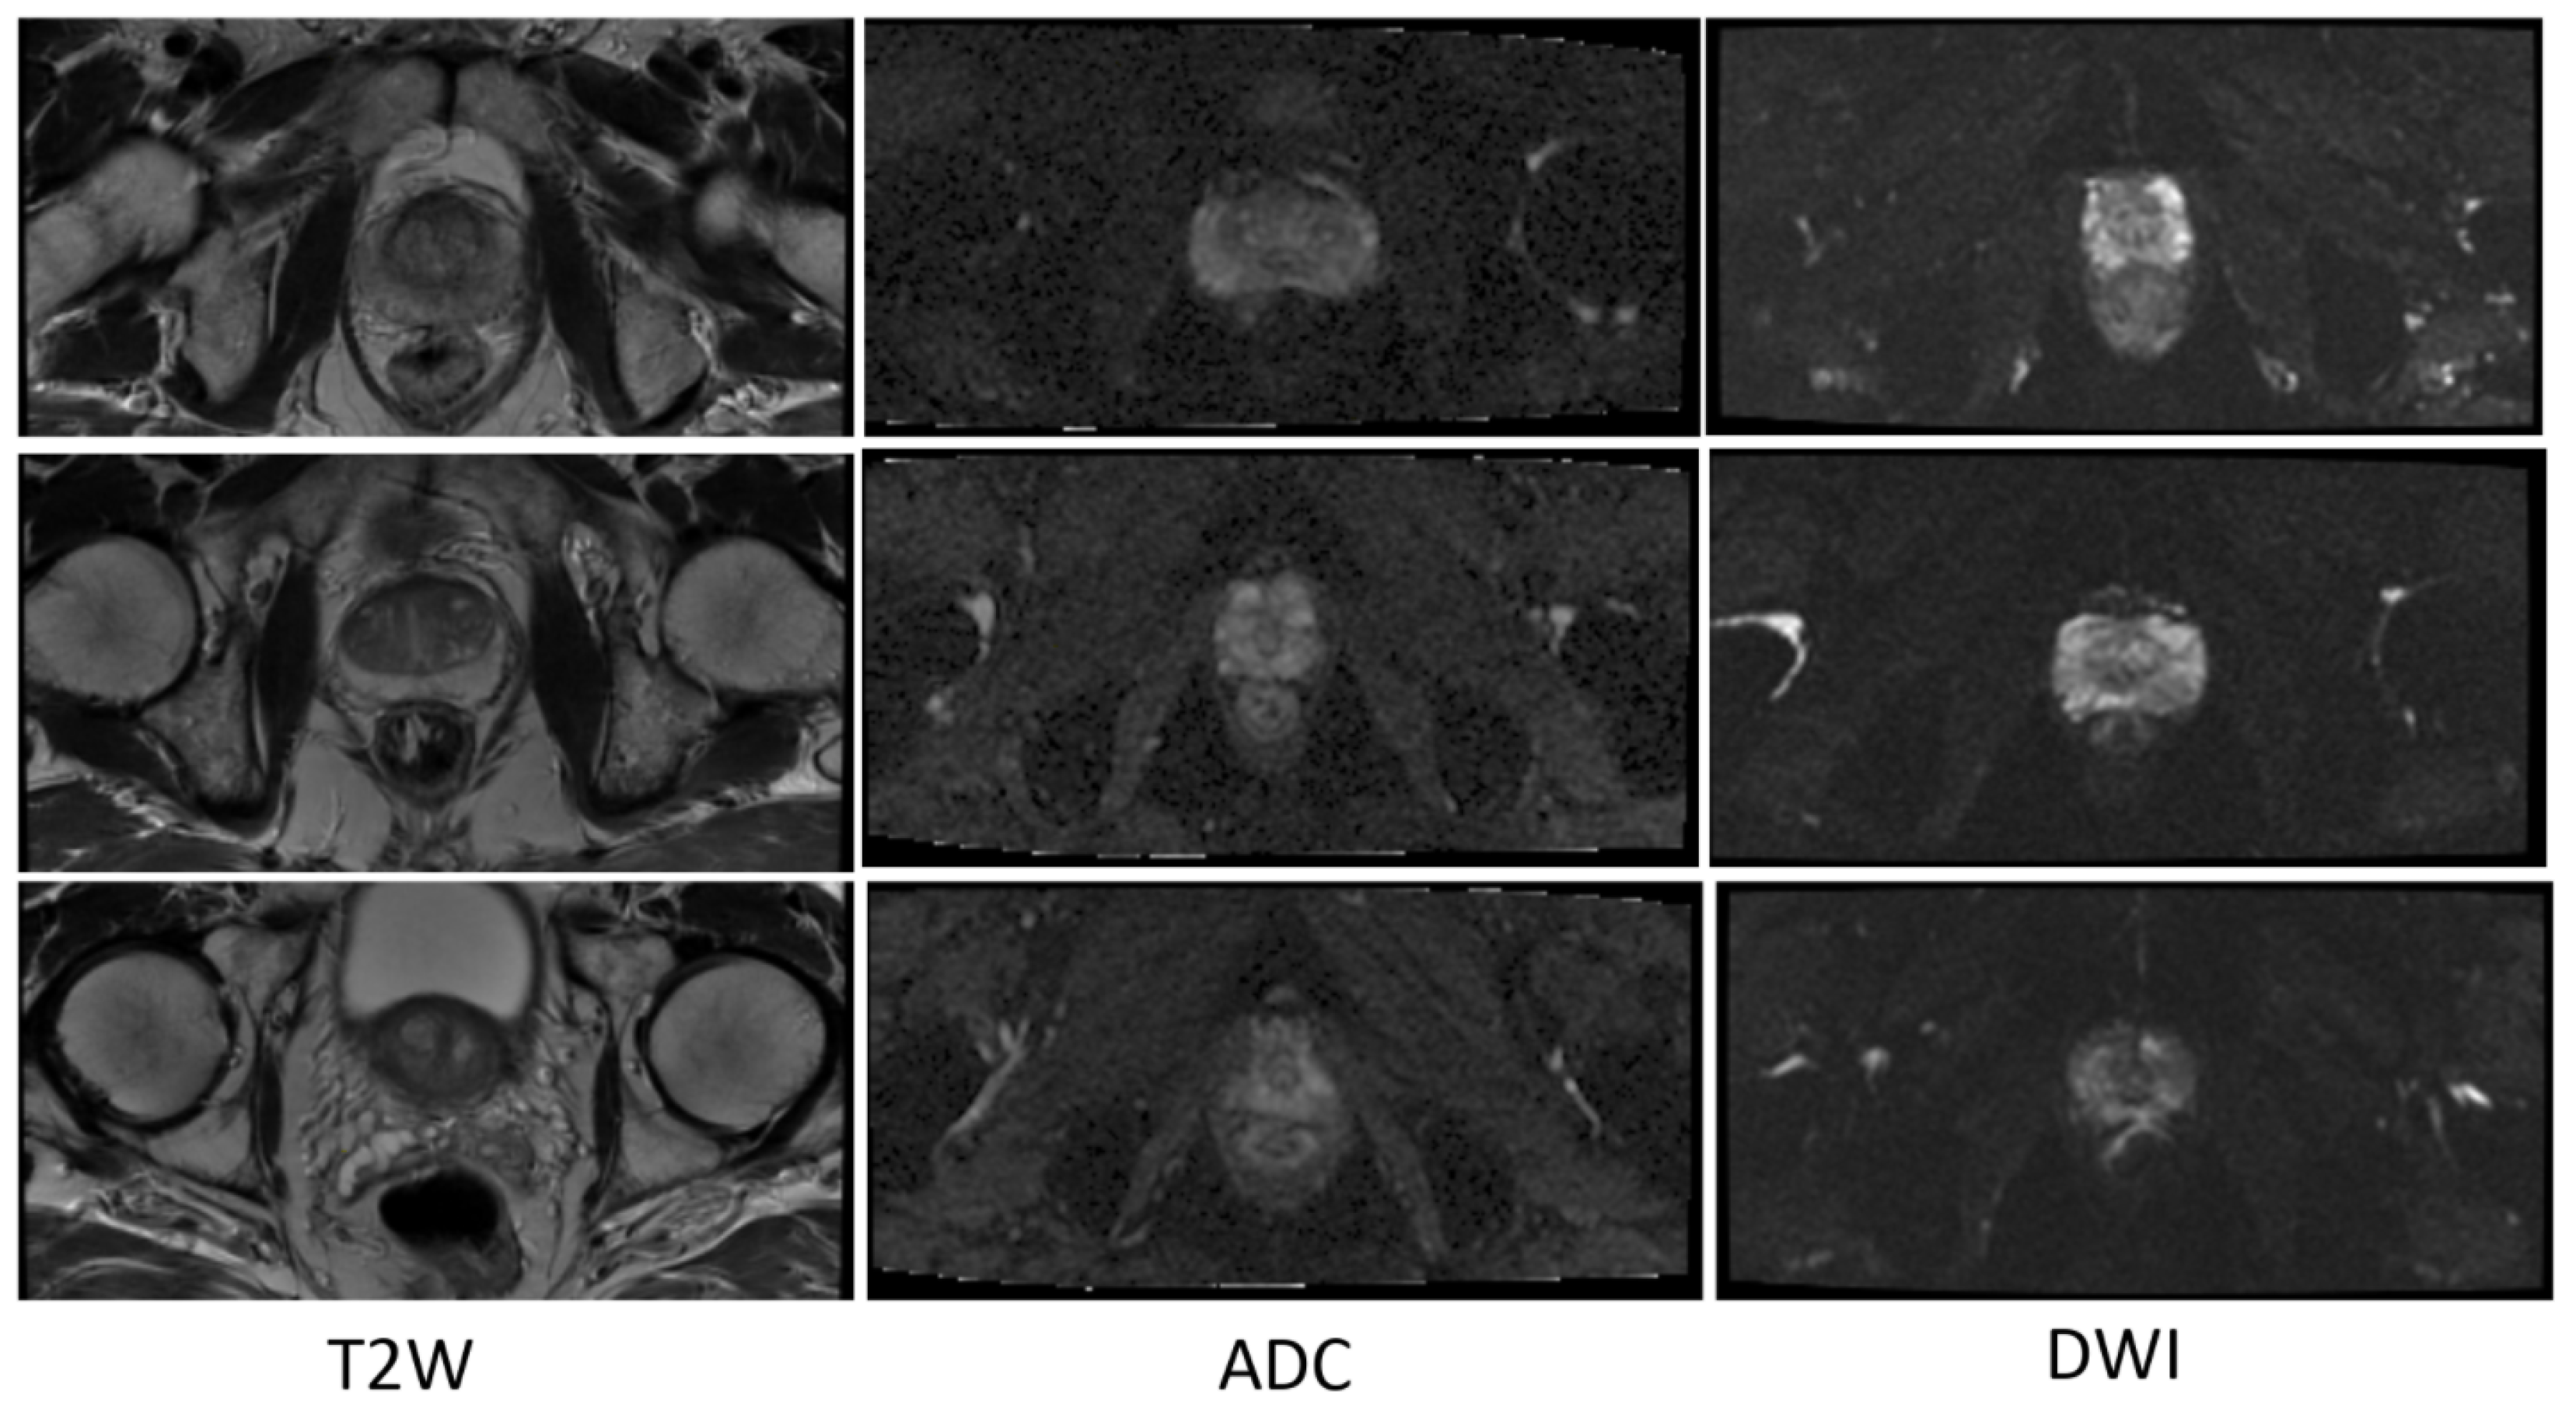

In terms of the T2W modality, similar outcome was achieved with regards to the training samples used during learning procedure for the cGAN model. The combination of raw and GNA was the best in the cGAN model; while the combination of raw and SP obtained the best output results in the cycleGAN model. To justify this by investigating the T2W modality images, we observed that the images in this modality show anatomy, especially the peri-prostatic structures, more clearly than other modalities. Figure 6 shows that ADC and DWI images have low signal around the prostate compared to the T2W modality. Superpixelizing the T2W images groups the pixels better and makes the surrounding anatomy more visible for the cycleGAN network. In the cycleGAN model there are two different domains and there is no paired input-output relation between them. The generators are penalized by the adversarial loss with the cycle consistency loss, which forces the generators to not only do the segmentation but also synthesize the original MR image from the created mask back again. As a result, the network learns a mapping between the training images and their masks and vice versa. Therefore, for the SP approach, learning is more optimised. When we compare the results of the raw plus SP images on the three modalities in the cycleGAN model, it is also consistent with this result that training using the T2W modality images obtained the best results (with DSC values of 0.748) while the DSC outcomes for DWI and ADC modalities were 0.702 and 0.710, respectively. For the DWI modality, the best results for the cGAN and cycleGAN models were achieved by using the raw plus MM images as the training set. The MM approach removes the unnecessary details from an image helping the network to focus on prostate tissue as the target part of the image during the training process. It shows consistent results with regards to the three evaluation metrics. The ROC curves and AUC values for these networks, applied to three modalities (ADC, DWI and T2W), are shown in Figure 7.

Figure 6.

Some examples of T2W, ADC and DWI MR images from our dataset, which demonstrates that DWI and ADC modalities have lower signal around the prostate compared to the T2W modality. Scaled images are shown in Figure A2 for better visualisation.

Figure A2.

Some examples of T2W, ADC and DWI MR images from our dataset, which demonstrates that DWI and ADC modalities have lower signal around the prostate compared to the T2W modality.